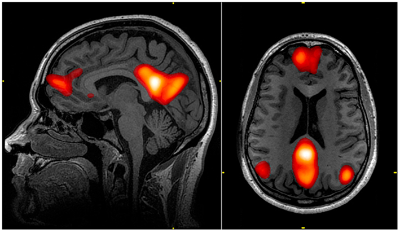

명상은 과활성된 DMN모드를 진정시킨다.

꽤나 현대에 와서야 존재가 밝혀진 DMN모드는 몰입할 거리가 없을 때 마음이 방황하는,

일종의 산만한 멍때리기 상태일때 활성화 되는 모드임

나 이런사람이야~ 불교식으로 말하면 아상을 짓는 부분이기도 함

우울증 환자들의 뇌를 분석한 결과 이 모드가 과활성 되어있었음

자세한 설명까지 적자면 너무 길어짐으로 링크로 대체 https://digthehole.com/4923

그리고 fMRI 스캔에서는 전전두피질 부위와 디폴트 영역 간의 연결이 증가할수록 사이토카인의 감소 폭이 더 큰 것으로 발견되었다.